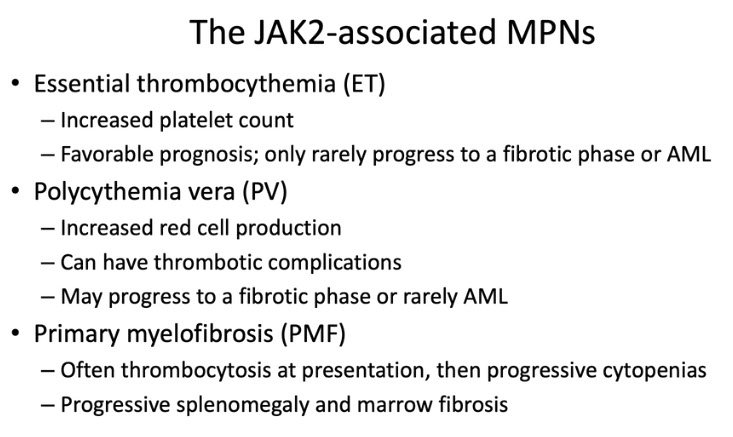

Essential Thrombocythemia (ET)

- Thrombocytosis in excess of 1000 X 109/L

- Disease associated with JAK2 gene mutations (~50% patients have them) and MPL and CALR gene mutations

Polycythemia Vera (PV)

Panmyelosis and specifically increased red cell mass (RCM)

Molecular basis is JAK2 (Janus kinase 2) gene mutations (usually JAK2 V617F), >98% patients

PMF

Primary Myelofibrosis (PMF)

Dz assoc c JAK2 gene mutations (~50% pts) and MPL and CALR gene mutations

Px

Survival from months to decades depending on the stage at first diagnosis

Death from BM failure, portal HTN, thrombosis, CHF and AML

- 5%-8% transform into AML.